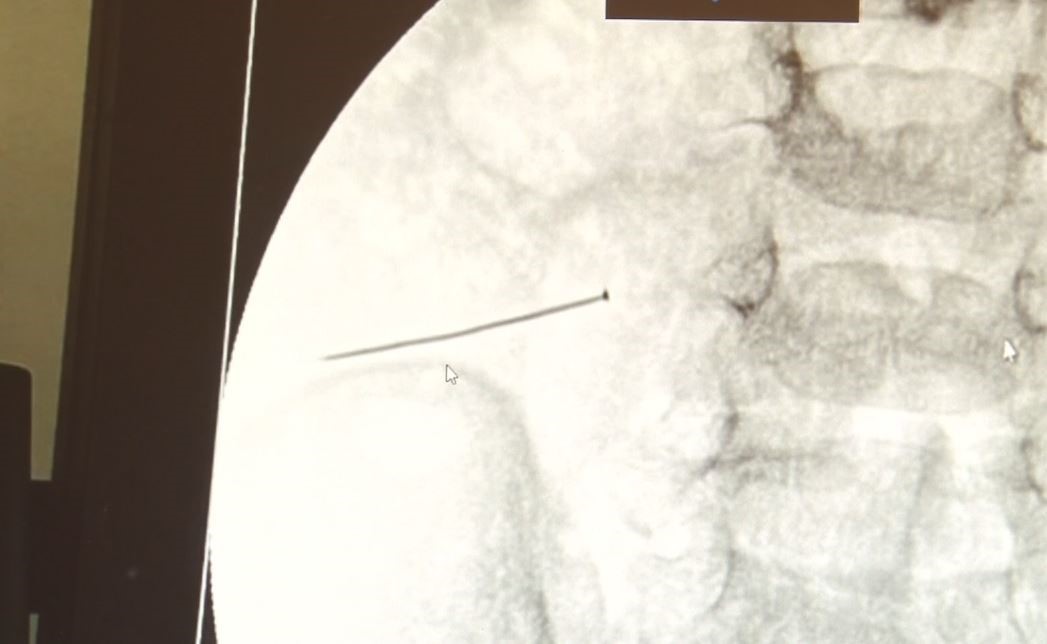

Kağızman Devlet Hastanesi’nde karın kesisi ameliyatı